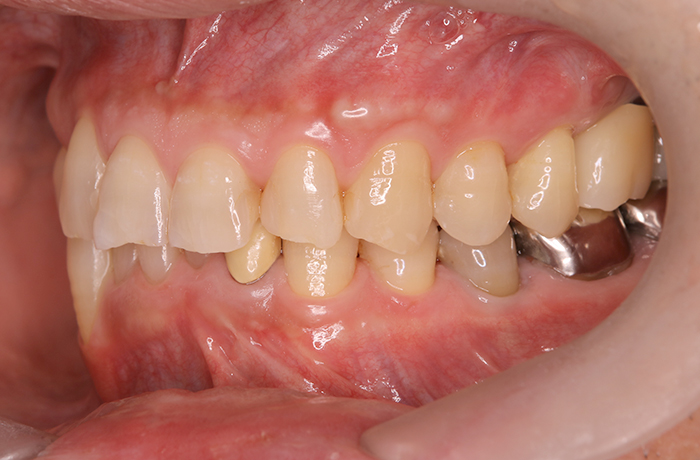

治療後

治療終了後の完成した口腔内と

レントゲン写真

サイナスリフト部の骨再生は良好で、インプラントの安定性も高く、骨吸収や透過像はありませんでした。

最終補綴装着後は咬合バランスが改善し、良好な咀嚼機能が回復。審美性にも優れ、患者様にもご満足いただけました。